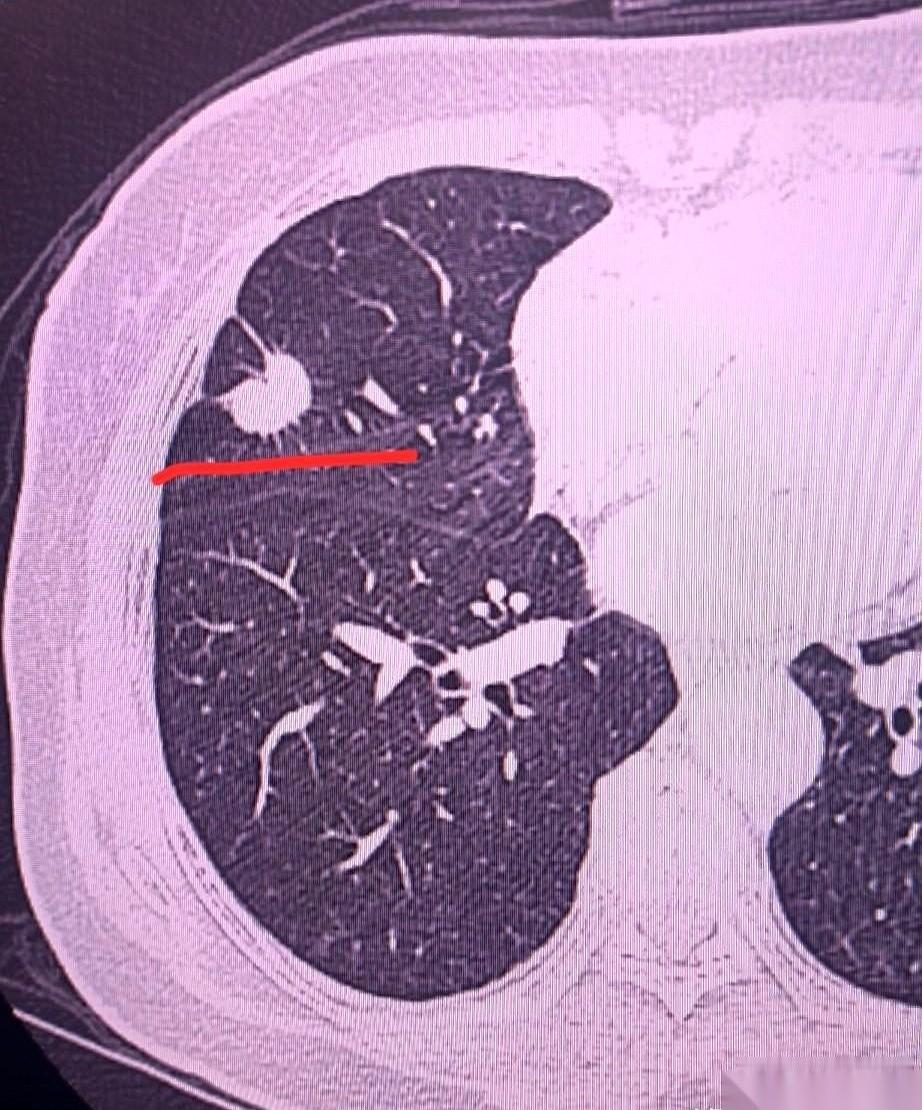

要不是这场甲流,我们单位的郭主任,可能真就奔着“鞠躬尽瘁”去了。 字面意思的那种。 48岁,办公室主任,二十年没请过假,你说这是个什么概念?就是个铁人,一个上了发条就停不下来的陀螺。 前两天烧到快40度,实在扛不住了,才被架到医院。 咳得撕心裂肺,医生说,顺道拍个CT吧。 他本来还嫌麻烦,说忙。 呵,忙。 结果片子一出来,所有人都傻了。 右肺那个结节,不是新东西。两年前体检就有了,当时才0.3公分,医生轻飘飘一句“建议复查”。 谁当回事儿了? 郭主任没当回事儿,他忙着开会,忙着写材料,忙着…….反正就是忙。 两年。 就两年时间。 那个当初不起眼的小点,硬是给“忙”大了一圈不止,一公分多,边缘毛刺、分叶……CT报告上的词儿,都不用医生翻译,光看着就浑身发冷。 癌。 你说这事儿多讽刺? 一场差点要了他半条命的甲流,反而可能救了他一条命。 它用最粗暴的方式,把他从办公桌上掀翻,摁在了病床上,逼着他去看那张两年前就该复查的片子。 人啊,总觉得自己牛逼,能搞定一切。 跟工作横,跟deadline横,跟KPI横……觉得自己无所不能。 你跟身体横一个试试? 它才是你最大的老板。 它让你歇,你不敢不歇。它想让你停,你就必须停。 不然,它直接让你 Game Over。